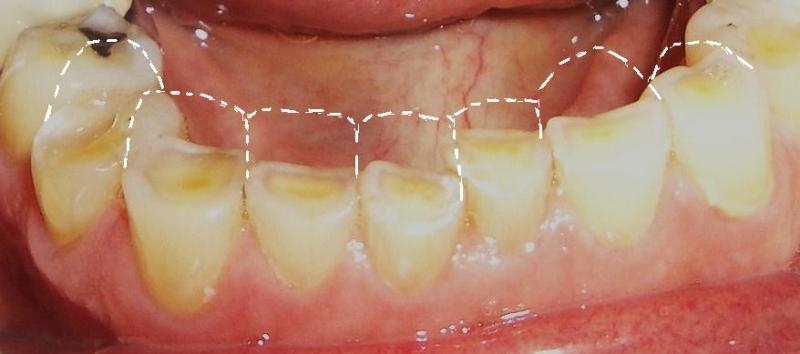

Due to the effect of tooth wear, some degree of enamel loss is always present. We follow the concept of minimally invasive treatment which means we preserve as much of your tooth structure as possible and aim to just adding 'enamel' back to the tooth. In essence you have already done a big part of tooth 'preparation' for us and we therefor just want to add on. Naturally we also place a high emphesis on prevention which means that we want to protect your teeth against any further wear.

Teeth that have been worned down cannot just be restored or build up as often there is NO SPACE for the material. The opposide jaw bites down into these areas creating the wear in the first place and due to this worned bite, material cannot just be added since the bite will then be too high. The dentist is forced to removed even more tooth structure to create vertical space to build some protective layer of material over these worned areas. This is not ideal and a new workflow was created to overcome this method to restore the worned teeth with little to NO tooth reduction.

This shortage of space is the main reason why treating tooth wear is so complex. We cannot just restore the one problem tooth in question and often the whole arch or both arches(all the teeth) need to be restored simultanously and raised to a new vertical dimention. This new layer of 'enamel' or material will be covering the whole biting surface and thus needs to be strong and well planned.